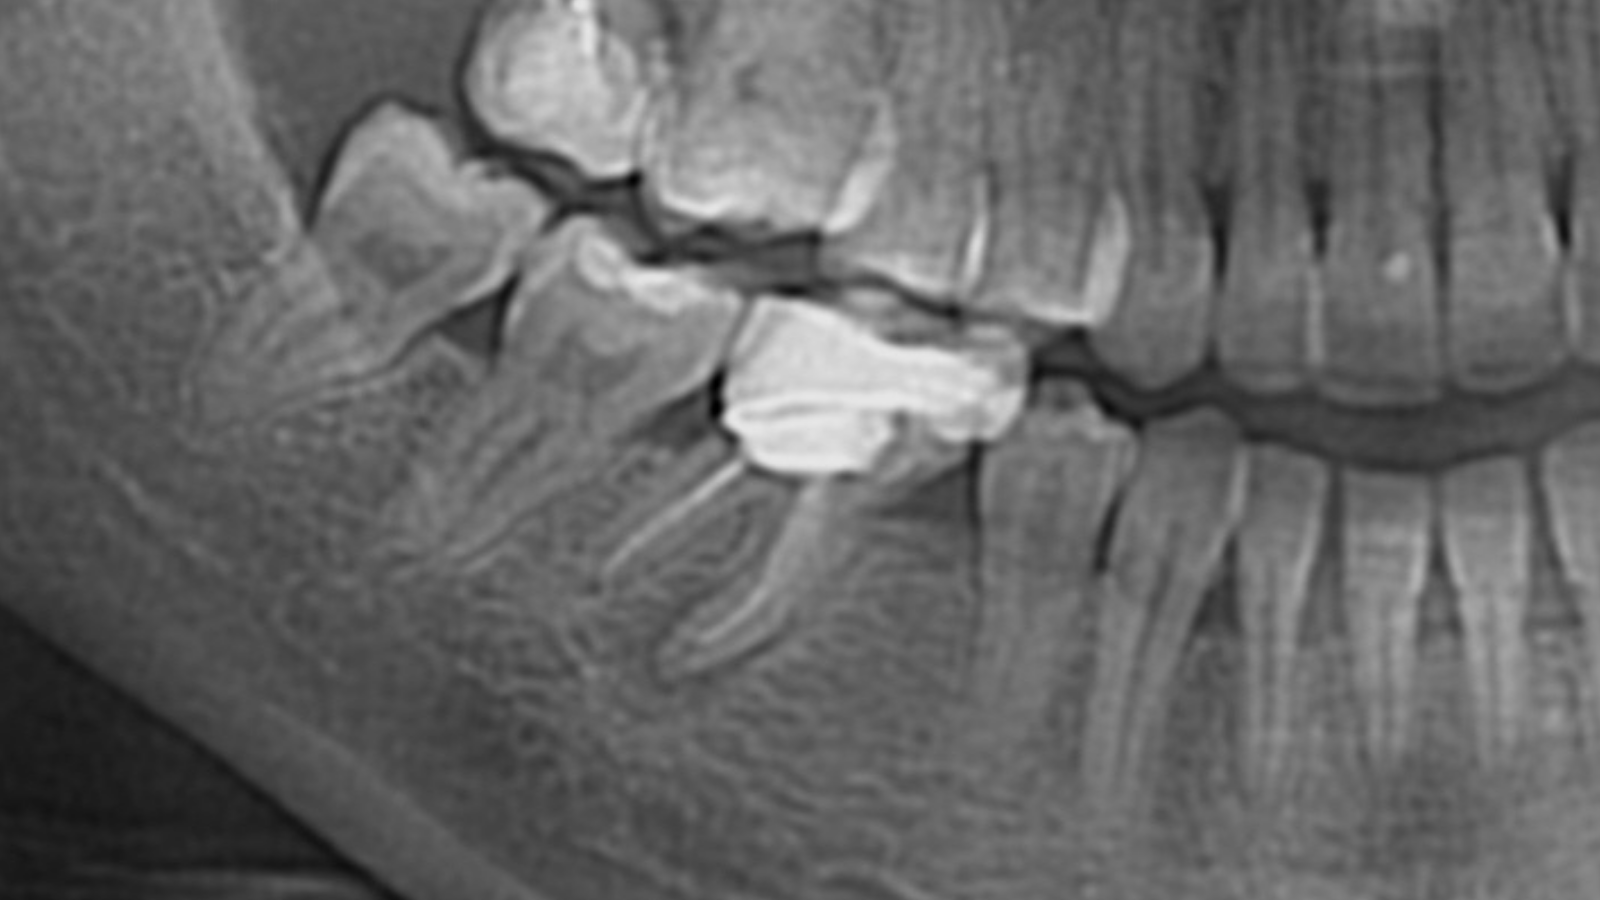

Molaire inférieure droite : infection apicale et traitement canalaire

Une jeune patiente se présente avec une infection au niveau de sa molaire inférieure droite. Sur la première image, on observe un halo grisâtre autour des sommets des racines, signe de résorption osseuse liée à l’infection.

La prise en charge a consisté en une dévitalisation réalisée en 3D, avec respect des principes essentiels : désinfection rigoureuse et maîtrise des longueurs de travail au niveau des racines.

Sur la seconde image de contrôle, le résultat est visible : disparition du halo, traduisant une évolution favorable.